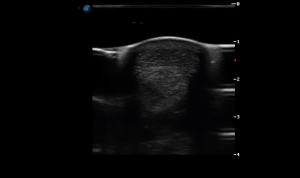

SIMON Ultrasound Database

This ultrasound database is a free resource for students and doctors!

Our collection includes videos of dogs, cats, horses, cows, humans, and many other species!